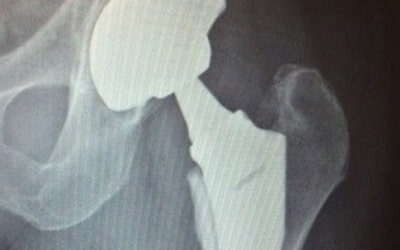

- Joint replacement of the hip and knee

- Minimally invasive hip replacement and knee surgery

- Outpatient total hip and knee surgery